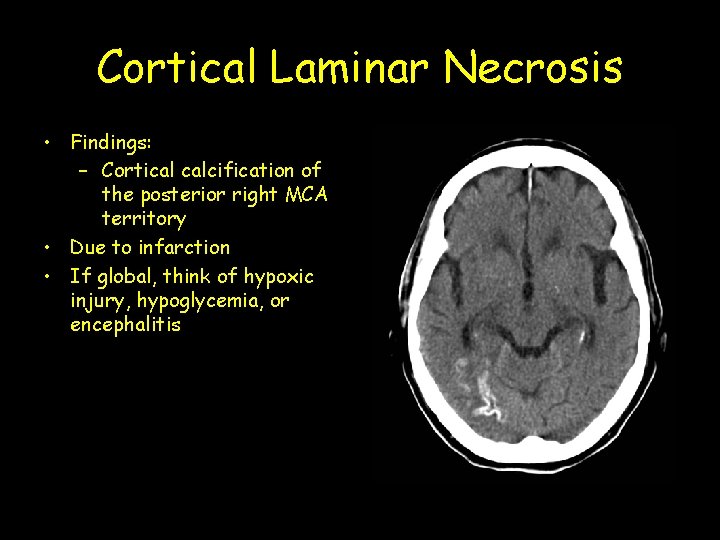

Cortical Laminar Necrosis • Findings: – Cortical calcification of the posterior right MCA territory • Due to infarction • If global, think of hypoxic injury, hypoglycemia, or encephalitis